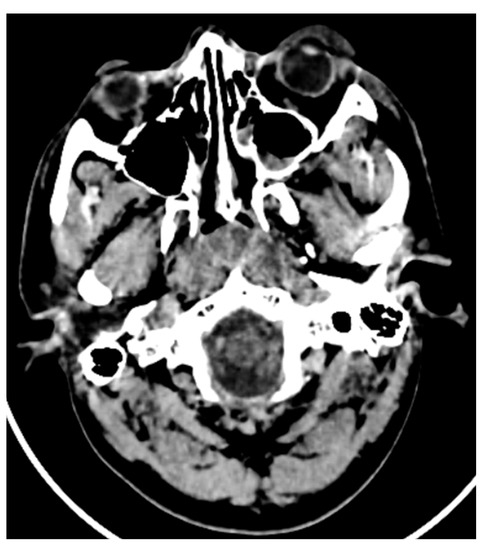

In a case of zygomatic complex fracture, orbital involvement revealed a linear minimally displaced fracture noted involving the left zygomatic arch, the lateral wall of the left orbit. A comminuted displaced fracture involving the lateral wall of the left maxillary sinus with fracture fragments lying inside was associated with hemosinus (Figure 4 and Figure 5). However, the soft tissue window failed to reveal further details with regard to the pterygoid muscles and orbital volume. Other than the displacement and type of fractures, the extent of orbital involvement also determines surgical treatment in this case. The most common cause of posttraumatic enophthalmos is increased orbital volume [6]. All images were taken using 5th generation mono-energy CT machines with standard exposure parameters of 140 kvp, 200 mA soft tissue with a slice thickness of 0.5–0.6 mm, and bony windows.

Figure 4. CT axial section of a pan-facial trauma: a comminuted displaced fracture involving the lateral wall of the left maxillary sinus with fracture fragments lying inside, associated with hemosinus.

Figure 5. Comminuted displaced fracture involving the lateral wall of the left maxillary sinus with fracture fragments lying inside, associated with hemosinus. The soft tissue window failed to reveal further details with regard to the pterygoid muscles and orbital volume.